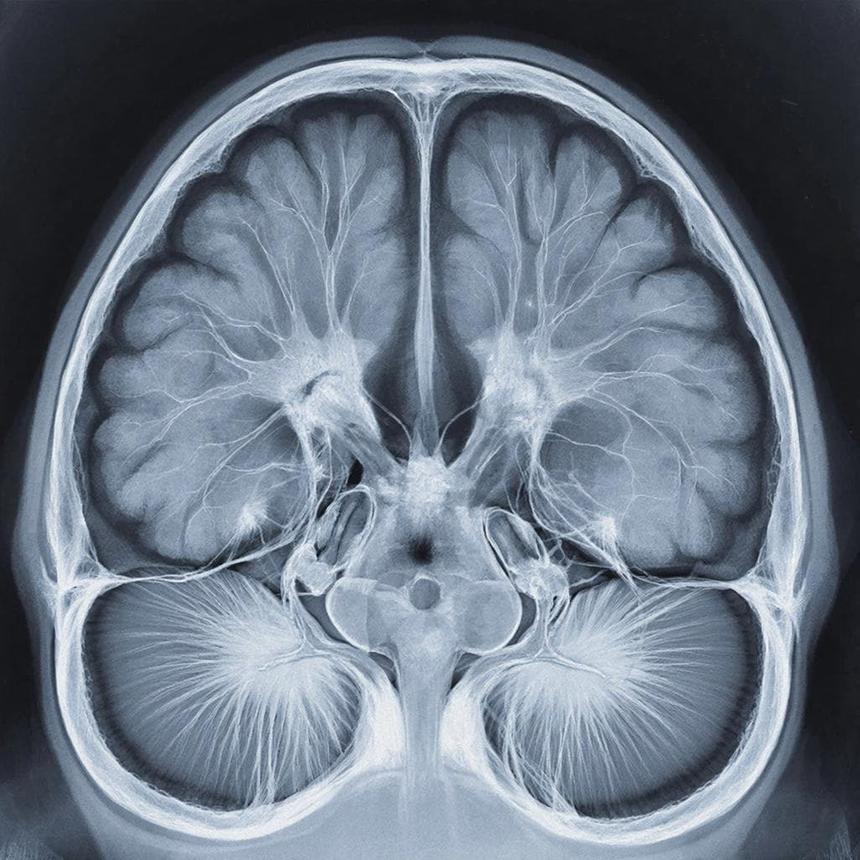

На Чукотке нейросети обучат расшифровывать КТ мозга

На Чукотке до конца 2026 года в окружной больнице планируют внедрить анализ КТ головного мозга и диагностику патологий по снимкам сетчатки глаза с помощью нейросетей. Искусственный интеллект уже работает в регионе с 2024 года на платформе «МосМедИИ» и проанализировал более 2,5 тысячи снимков. На развитие технологий направят около 8 млн рублей из федерального и окружного бюджетов.

До конца 2026 года в больнице планируют подключить анализ компьютерной томографии головного мозга, а также запустить диагностику заболеваний по снимкам сетчатки глаза. Оба направления призваны повысить качество медицинской помощи в отдалённых районах, где доступ к узким специалистам ограничен. На эти цели из федерального и окружного бюджетов выделят порядка 8 млн рублей.